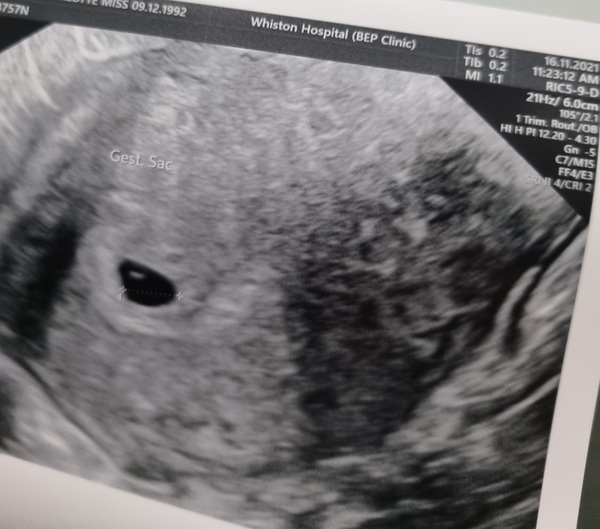

gezelligheid · 16/11/2021 18:59

I have to go back for another scan on November 25th but the scan today shows that baby is growing in the right place! Such a relief after my ectopic last year! The sonographer said although I'm 6 weeks from LMP, I'm looking more like just on/approaching 5 weeks Smile

Tracking your cycle and possible BFP using RHR - part 6

GlassLily · 17/11/2021 01:24

@gezelligheid Lovely, congratulations! You must be so relieved. And great to get another one next week! So many scans Grin